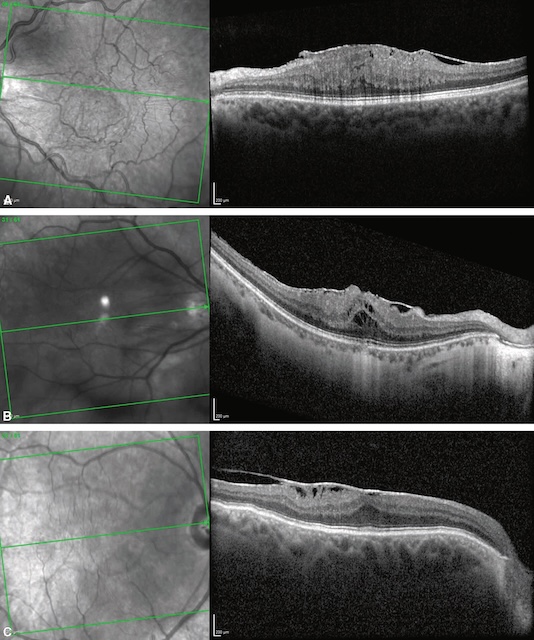

Dans ce cas, la séparation du vitré postérieur de la région maculaire va être associée à la prolifération d’un tissu fibreux à la surface de la macula que l’on appelle « membrane épi-maculaire » (fig. 7.4). Ces membranes peuvent rester paucisymptomatiques ou, au contraire, se rétracter et alors être responsables d’une baisse de vision et/ou de métamorphopsies. Au fond d’œil, elles prennent un aspect brillant (« reflet cellophane ») associé de manière variable à une distorsion du tissu rétinien adjacent et des vaisseaux. L’examen clé est l’OCT maculaire (voir fig. 7.4 et fig. 7.5A-C) qui confirme le diagnostic et objective l’augmentation secondaire de l’épaisseur rétinienne (reflet du degré de contraction de la membrane). Lorsque la baisse d’acuité visuelle associée est importante, la membrane peut être « pelée » chirurgicalement par voie de vitrectomie.

A. Reflet cellophane visible au fond d’œil avec plis et tractions des vaisseaux de petit calibre. B. Cartographie OCT avec épaississement maculaire (couleurs chaudes). C. Ligne hyperréflective visible à la surface de la rétine (flèches), responsable de la perte de l’aspect d’entonnoir fovéolaire « normal ». Noter le décollement du vitré postérieur en regard (astérisque).

La partie A montre une photographie couleur du fond d’œil centrée sur la macula, avec un reflet brillant, une légère distorsion rétinienne et un plissement en surface évoquant une membrane épirétinienne. La partie B présente une carte de l’épaisseur maculaire obtenue par tomographie en cohérence optique (OCT), avec un épaississement central de la rétine représenté par des teintes rouges et jaunes, traduisant une traction rétinienne. La partie C montre une coupe transversale maculaire en OCT illustrant une membrane épirétinienne hyperréflective provoquant une distorsion de la surface rétinienne et un épaississement. Des flèches indiquent les zones de plis rétiniens et de traction. L’astérisque marque une séparation partielle du vitré postérieur. Un carré en bas à gauche précise l’orientation de la zone maculaire analysée.

Parties A à C. Série d’images obtenues par tomographie en cohérence optique (OCT) illustrant une membrane épimaculaire. Chaque partie comporte à gauche une image du fond d’œil en infrarouge avec des lignes de balayage vertes superposées, et à droite, la coupe transversale OCT correspondante. La partie A montre une surface épirétinienne épaissie et plissée avec des replis rétiniens. La partie B révèle une déformation plus marquée du contour maculaire avec distorsion et possibles modifications sous-rétiniennes. La partie C présente une membrane plus fine avec une traction limitée aux couches rétiniennes internes.